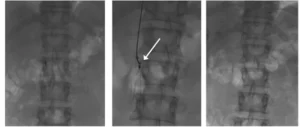

Trombosi venosa iliaco-cavale. Trombolisi reolitica (freccia bianca). Risultato finale.